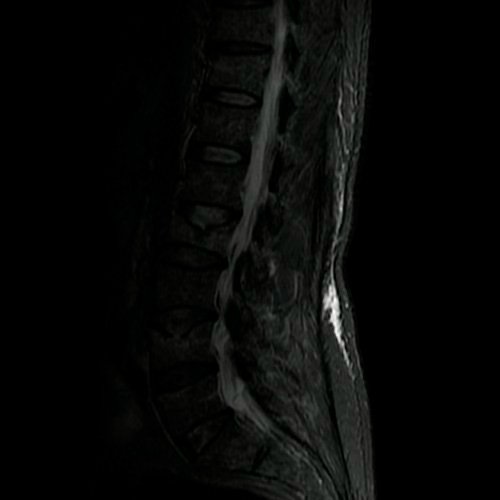

- Resonancia magnética de columna lumbar (28/08/2025): fractura aplastamiento de L2, a expensas de su platillo superior, que compromete el 60% de su altura. Fractura aplastamiento de L4 y L5, a expensas de platillos superiores, que afecta menos del 30% de la altura del cuerpo vertebral, sin desplazamiento. Estos cuerpos vertebrales presentan impronta de Schmorl en la placa terminal superior y resultan hiperintensos en STIR, hipointenso en T1, hallazgo compatible con edema óseo.

- Tomografía de columna lumbosacra (Día 0): Contamos con TC previa del día 04-09-2025 y RMI del día 28-08-2025. Hiperlordosis lumbar. Eje lumbar se encuentra desviado hacia la derecha. Persiste, de mayor jerarquía que en TC previa, la reducción de altura de los cuerpos vertebrales de D12, L2, mayor al 50%, con afectación del muro posterior. También se observa reducción del 30 % del cuerpo vertebral L4 y L5. Hallazgos en relación a fracturas aplastamiento patológicas. Además se observa marcada osteopenia generalizada. Disminución de la altura intervertebral de L2-L3 y L3-L4, a nivel de su margen posterior. Los demás espacios discales visualizados son de altura conservada. No se observan signos de protrusiones ni hernias discales. Ligera rarefacción del TCS paravertebral.